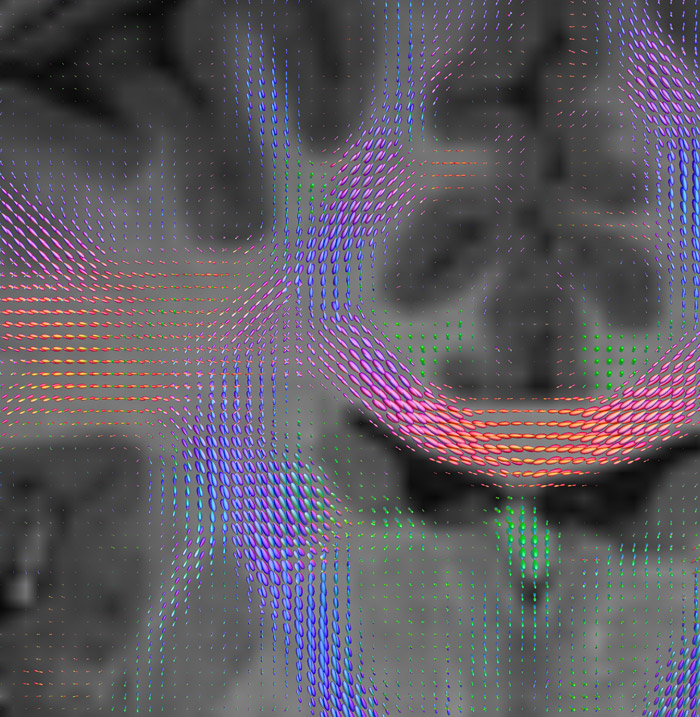

CSD of multishell DWI results in the white matter FOD at each voxel. Unlike the conventional diffusion tensor model, this approach enables accurate modeling of multiple fiber populations within a single voxel.

Crossings of the corpus callosum, corticospinal tracts, and the superior longitudinal fasciculus are shown.

Crossing fibers of the corpus callosum bordered by the superior longitudinal fasciculus as well as within in the pons.

All images were created from the same acquisition in a child using Ingenia 3.0T CX and 32-channel dS Head coil. Diffusion data was acquired at b-values 0, 500, 1000, 2000, 3000. The use of high b-values (3000 s/mm2) effectively suppresses extra-axonal water signal and provides high angular resolution.